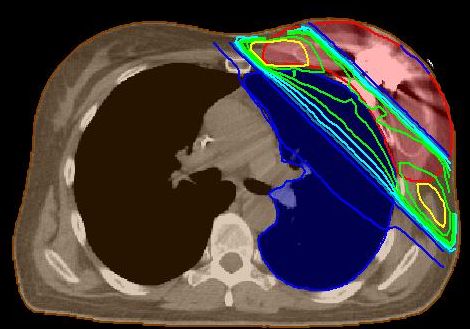

| Technik der perkutanen Bestrahlung |

| Inspiration |

Die Bestrahlung in Inspiration kann Herz und Lunge besser schonen. |